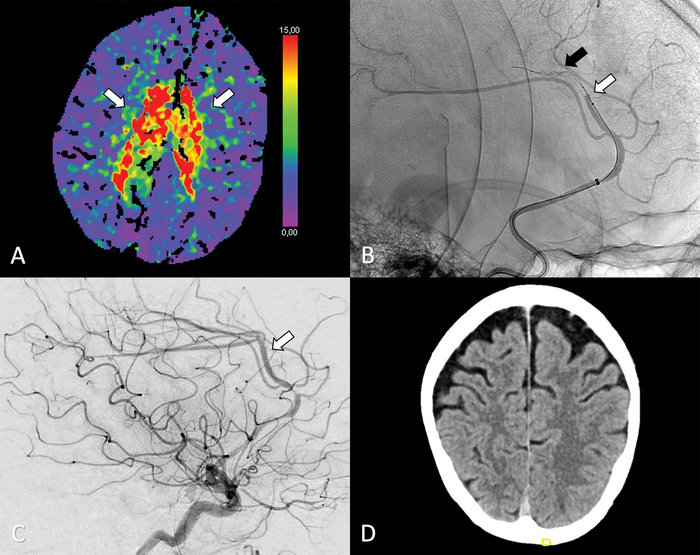

Recent advances in technology have made it possible to perform thrombectomy in some of the narrower vessels in the head—vessels like the anterior cerebral arteries that arise from the internal carotid artery. However, evidence supporting a potential benefit of thrombectomy for these vessels remains unknown.

As part of the Treatment fOr Primary Medium vessel Occlusion Stroke, or TOPMOST trial, researchers in Germany compared thrombectomy with medical treatment in 154 patients. The patients all had primary isolated anterior cerebral artery medium vessel occlusions, or obstructions. The patients underwent thrombectomy or best medical treatment, which typically involves medications to dissolve the clot and reduce blood pressure. In some cases, patients may receive intravenous thrombolysis, the introduction of clot-busting drugs to the bloodstream or directly to the site of clot.

The results showed that thrombectomy was a safe and technically feasible option. Within the first 24 hours after treatment, thrombectomy patients had similar outcomes to those who received best medical treatment alone with or without intravenous thrombolysis. Longer term, both groups had similar clinical and functional outcomes. Mortality rates were similar in both groups.

Selection of patients for thrombectomy remains a key issue, Dr. Meyer said, especially when patients are not eligible for randomization in a designated trial.